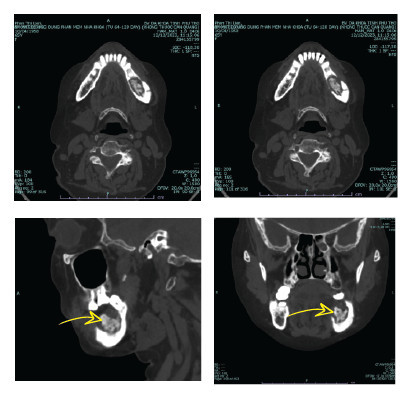

Tại đây, sau khi thăm khám và làm các xét nghiệm máu tổng quát, chụp cắt lớp vi tính vùng hàm mặt, người bệnh được chẩn đoán: viêm hoại tử xương hàm dưới bên trái trên người bệnh đái tháo đường (tại vị trí răng đã nhổ vẫn còn mảnh xương chết chưa được lấy hết).

Hình ảnh chụp cắt lớp vi tính vùng hàm mặt của người bệnh trước khi được điều trịHình ảnh chụp cắt lớp vi tính vùng hàm mặt của người bệnh trước khi được điều trị